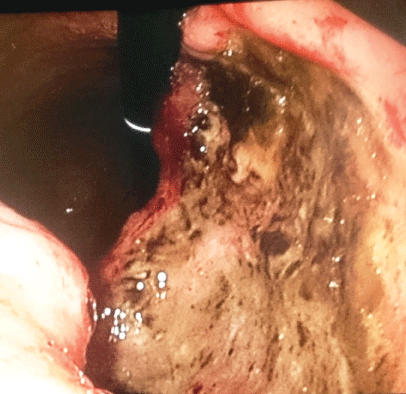

During the upper GI endoscopy, we noticed to our surprise the presence of a sizable ulcerative lesion occupying the second half of body of the stomach on the lesser curve, exactly above the gastric angle (Figure 1), which was covered by a black-yellowish coating with irregular margins and with no active bleeding. Apart from this finding, nothing else was revealed. Biopsies were taken with great difficulty due to the hard consistency of the ulcerative margins of the lesion. The tissues were sent for histopathological evaluation which revealed a high-grade gastric adenocarcinoma.

Figure 1: Endoscopic image, in retroflexion view, showing a large tumor on the lesser curve and posterior face, immediately above the gastric angle, confirmed on biopsies as a high- differentiated adenocarcinoma.